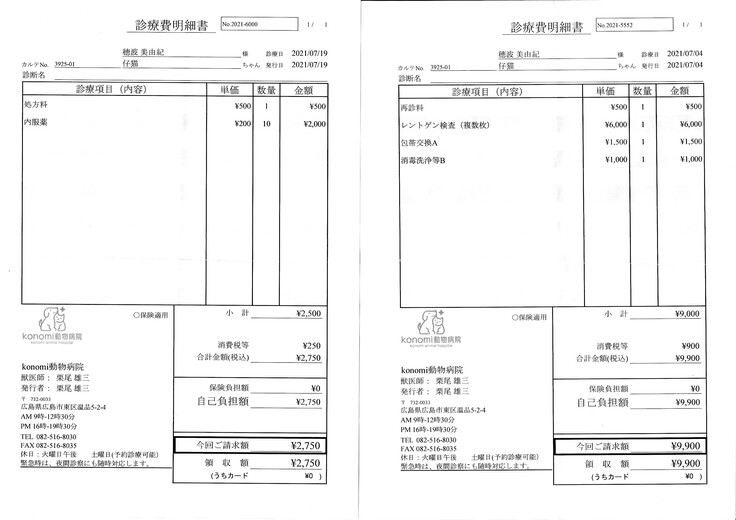

明細書

②退院後の飼育と治療

治療は続いていますが、これまでにかかった費用の一部を皆さまに助けて頂きたく、宜しくお願い致します。